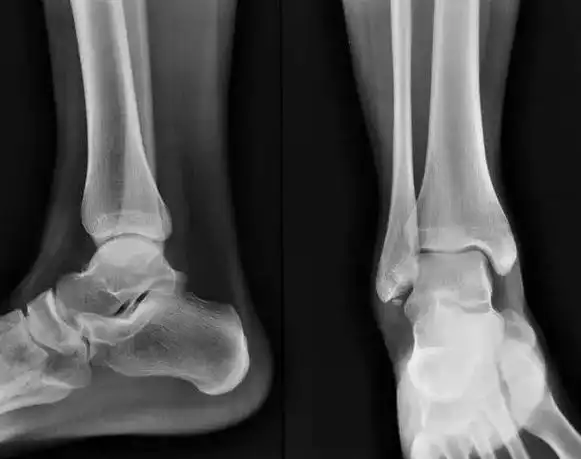

跟骨骨折基础篇

跟骨骨折病例

【读片】跟骨病例. [病例帖]